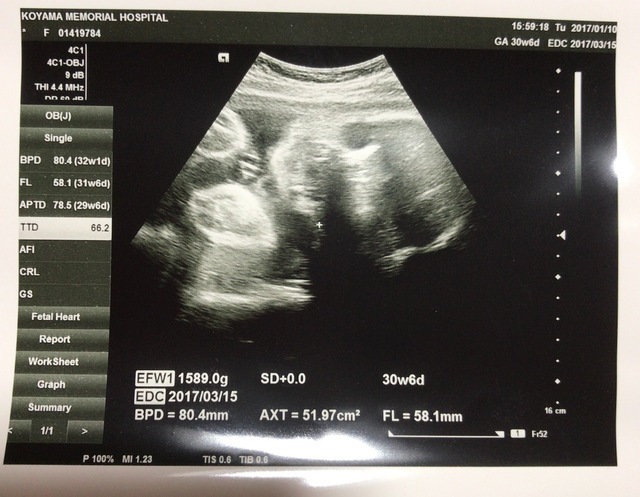

30週0日(30w0d・男の子)|mika1011 さん(26歳)

エコー写真撮影時のエピソード:

初めて4Dエコーを撮って、思っていたよりリアルで旦那さんと一緒に驚いたのを覚えています。4Dエコーで我が子の顔をはっきりと見て、お腹に赤ちゃんがいるという実感が一気にこみ上げてきて、感動で涙してしまいました(笑)